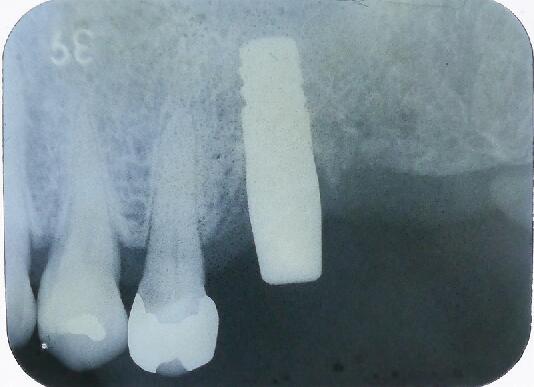

4ヵ月後のエックス線写真です すでに骨が出来ております

その後かぶせ物をして定期検診へ移行します